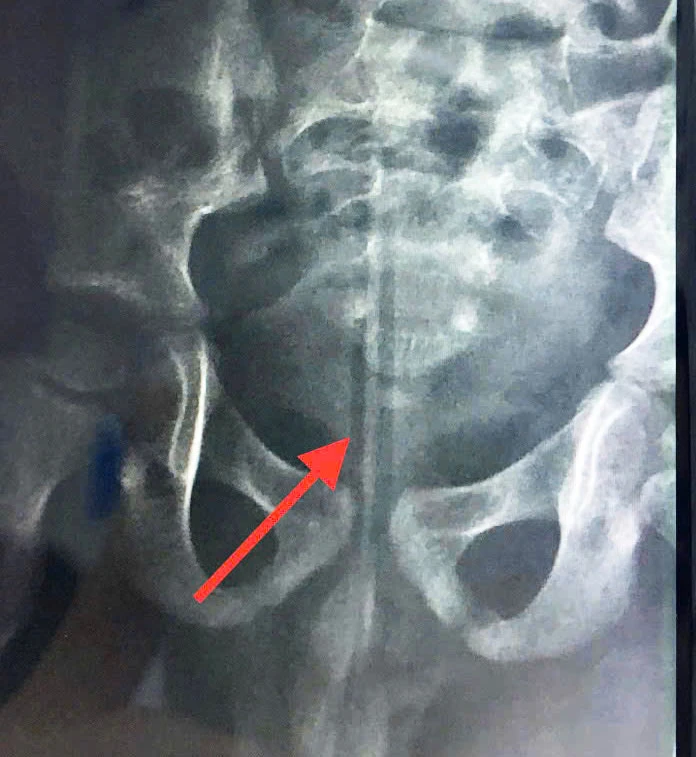

Gia đình lập tức đưa bé đến cơ sở y tế gần nhà. Kết quả chụp X-quang phát hiện dị vật trong khung chậu nên bé được chuyển đến Bệnh viện TP Thủ Đức.

Kết quả chụp X-quang phát hiện dị vật trong khung chậu bé trai 5 tuổi. Ảnh: BVCC